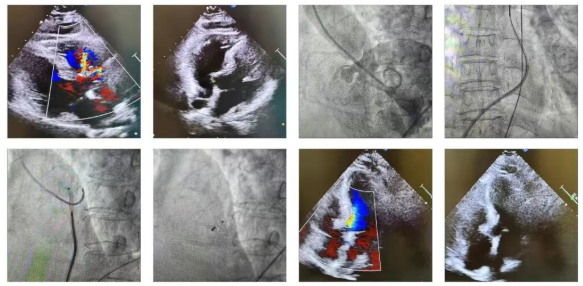

扬子晚报网2月23日讯(通讯员 刘柳 记者 姜天圣)近日,镇江瑞康医院心内科团队在首席专家严金川教授带领下,成功开展首例室间隔缺损封堵术,这是瑞康医院继房间隔缺损、动脉导管未闭、卵圆孔未闭封堵术后又一例结构性心脏病的成功治疗,标志着瑞康医院心内科在先天性心脏病救治方面迈出了新的一步。

患者为女性,73岁,因反复活动后胸闷、心悸,心前区杂音明显,心脏超声显示室间隔缺损(膜周部连续中断,可见回声失落约4 mm,左向右分流)。既往冠脉造影排除冠心病,以先天性心脏病,室间隔缺损入院。针对该患者心内科团队进行了充分的病例讨论,一致认为微创介入封堵术比较适合,术中通过股动、静脉穿刺,行“左心室造影”明确缺损情况。由于患者髂动脉、腹主动脉等非常扭曲,导致输送导管困难,无法在心腔内完成封堵器的释放,最后采用瓣上释放的方法完成封堵。封堵后听诊杂音消失,经心超检查及造影显示,明确缺损处无残余分流,各瓣膜未受影响,手术取得圆满成功。